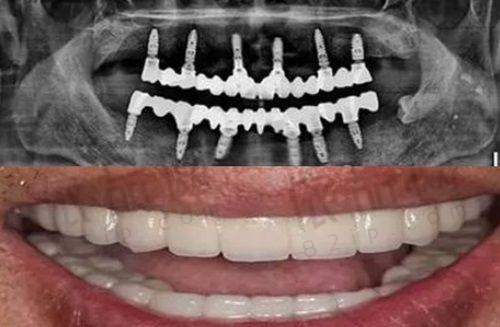

黎强医生专做种植牙和种植失败修复,尤其擅长高难度种植牙。像VIIV穿颧穿翼种植、即刻负重种植、局麻下改良颌外颧骨种植等,这些都是难度较高的种植技术,但他都能熟练掌握并运用。

无论是单颗种植牙、半口、全口种植牙或是穿颧穿翼等,黎强医生都比较擅长。对于不同的患者情况,他都能制定出合适的种植方案,满足患者的需求。比如有的患者可能只缺失了一颗牙齿,他可以精细地为患者进行单颗种植牙手术;而对于那些半口或全口牙齿缺失的患者,他也能通过精良的技术为患者修复牙齿功能。

他还善于将数字化导板导航技术与复杂种植病例相结合。这种结合使得种植手术更加精细和舒适,取得了相当好的成效。数字化导板导航技术就像是给手术加上了一个精细的“地图”,让医生能更正确地进行种植操作。

黎强医生特别擅长动态导航种植和导板种植。这两种技术的优势在于微创损伤小,在手术过程中能尽量减少对患者口腔组织的伤害,让患者术后修复更快。而且他对种植牙位置和层次的把控非常准,这就确保了种植的牙齿能够更好地与患者的口腔结构相匹配,提高种植牙的稳定性和使用寿命。